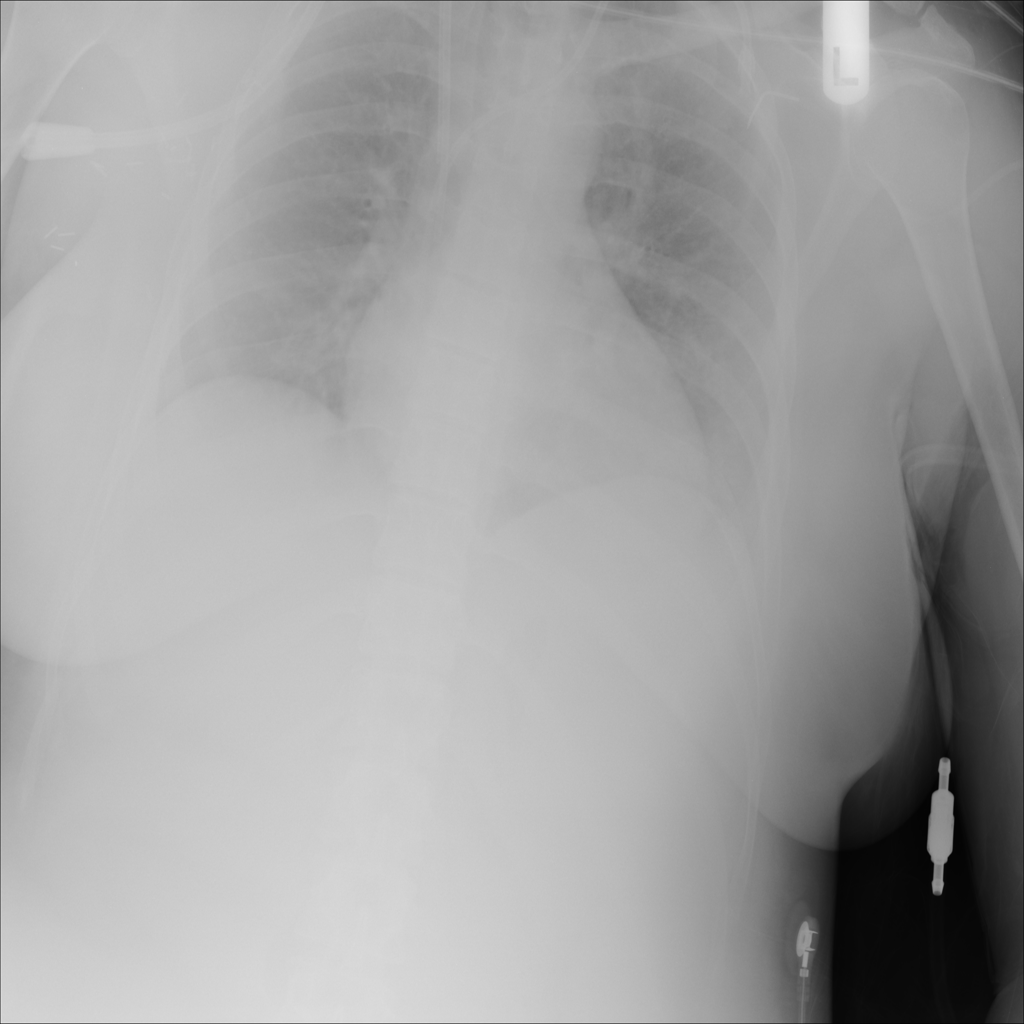

PAT-5B86 · IMG-009Edema

PAT-5B86 · IMG-009

PA